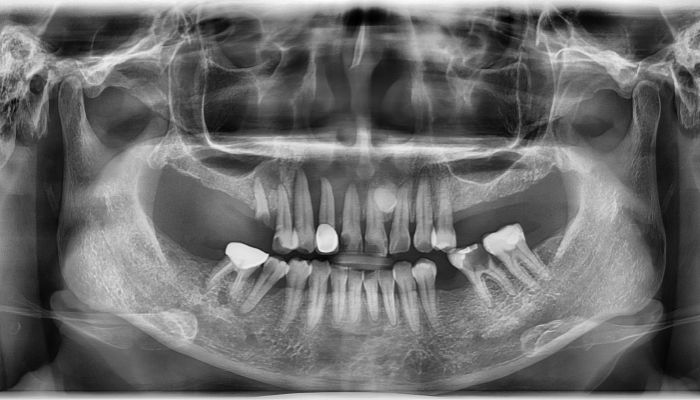

상악동거상술 수술사진

상악동거상술 전후 사례

• 식립전

식립후